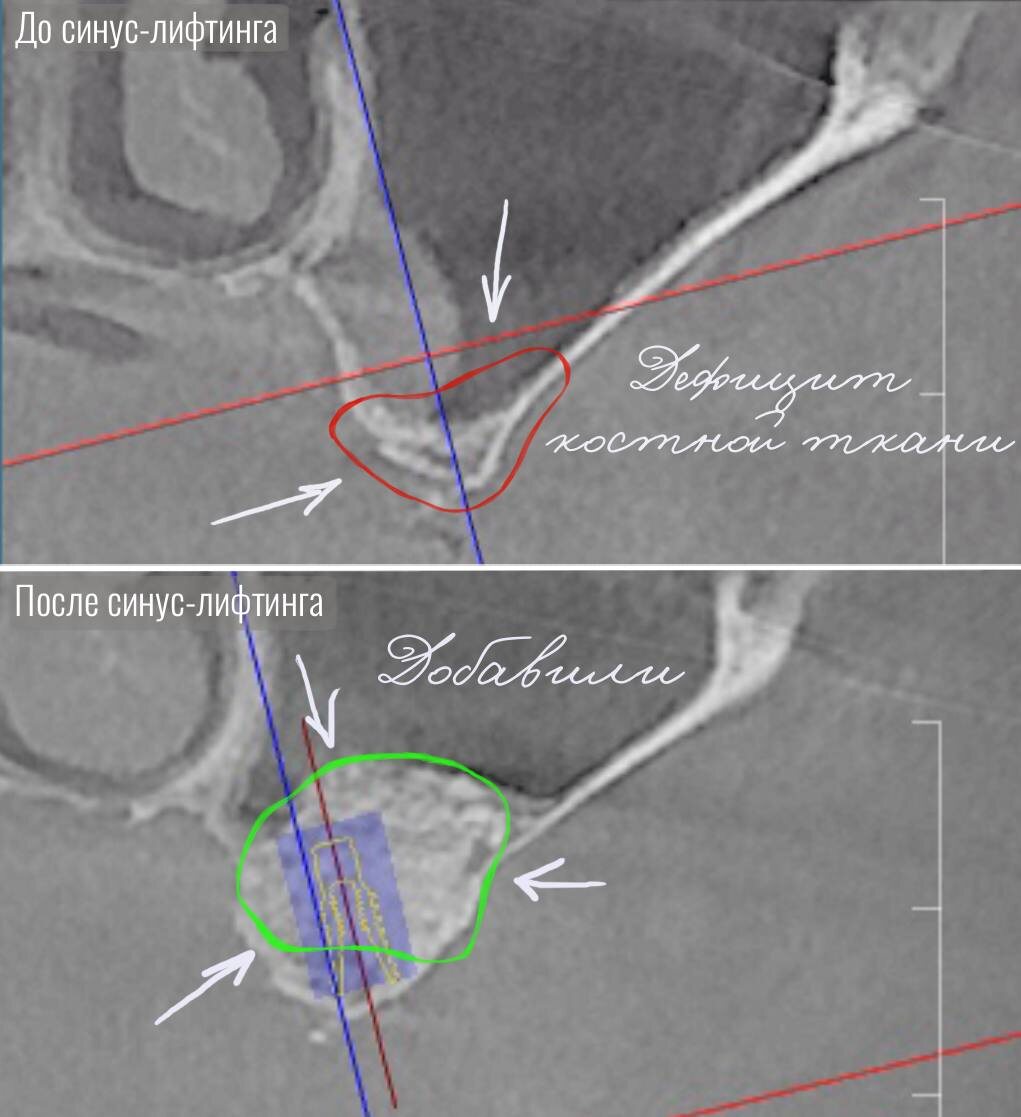

К нам обратился пациент с отсутствием жевательных зубов на левой стороне верхней и нижней челюсти. Так же наблюдался выраженный дефицит костной ткани, который делал невозможным установку имплантов без предварительного хирургического восстановления.

Вначале на верхней челюсти было выполнено два синус-лифтинга с левой и правой стороны, а также гингивопластика.

Синус-лифтинг — это операция по увеличению объёма костной ткани в области верхней челюсти под гайморовой пазухой.

Он проводится для надежной фиксации импланта. При недостатке костной ткани имплант просто не будет держаться. Процедура включает аккуратное поднятие слизистой оболочки синуса и введение костного материала (собственного, донорского или синтетического) для восстановления объёма кости.